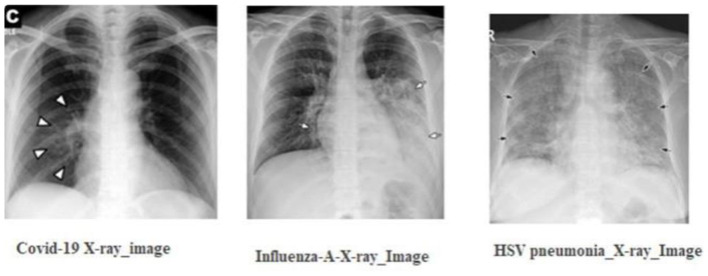

Leveraging compact convolutional transformers for enhanced COVID-19 detection in chest X-rays: a grad-CAM visualization approach.